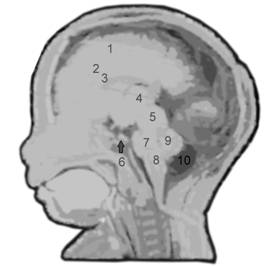

Fig. nr. 157 Planul VIII de sectiune sagitala prin creierul fetal pune in evidenta : 1 cortex cerebral, 2 corpus calosum, 3 cavum septi pellucidi ,4 talamus cu ventricul III,

5 lamina tecti, 6 glanda hipofiza , 7 puntea, 8 bulbul ( medulla oblongata ), 9 cerebellum, 10 cisterna magna . ( adaptat dupa England [5] ).

Planul VIII defineste profilul fetal in pozitie occipitoposterioara. Profilul de-vine vizibil de la sfarsitul trim I. In aceasta sectiune se pot oserva miscarile fiziologice fetale de deschidere a gurii, miscarea limbii, inghitirea, aspiratia de lichid amniotic.

Pozitia favorabila fetala poate pune in evidenta cavum septum pellucidi, corpus calosum (dupa 20 de sapt), lamina tecti, pons sau cerebellum.